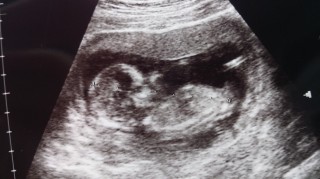

お顔バッチリうつりました!前回はあんな小さかったのにこんなに大きくなって....感動です!まだまだ心配だけどとりあえず一安心!

先月はあんなに小さかったのにこんなに大きくなっていて感動しました。旦那もすくすく育つ我が子に顔が緩みっぱなしです(^^)